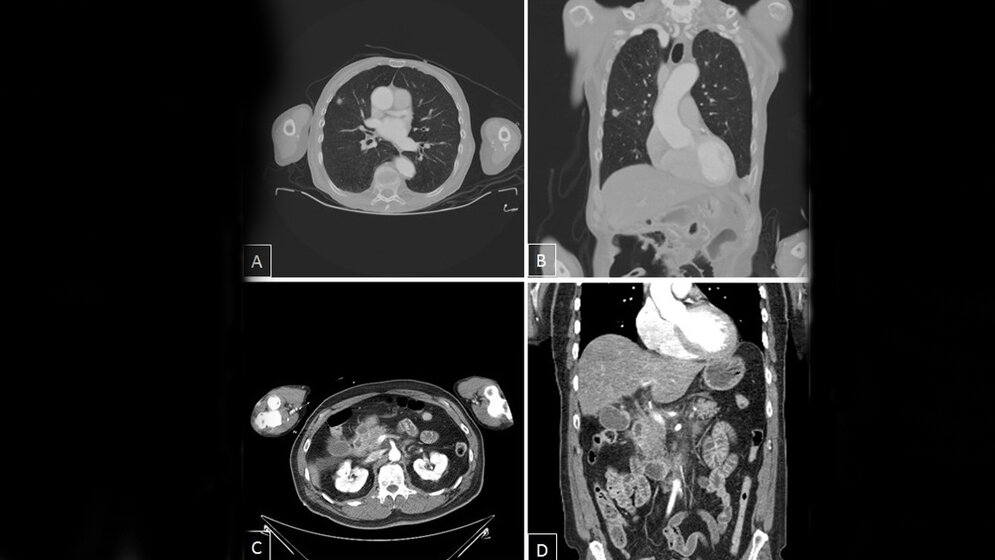

*A und B: Polytrauma-CT mit koronaler multiplanarer Rekonstruktion, Malignomsuspekte Lungenraumforderung rechts. Suspekt für ein peripheres Bronchial-CA.

C und D: Polytrauma-CT mit koronaler multiplanarer Rekonstruktion. Akute exsudative Pankreatitis.